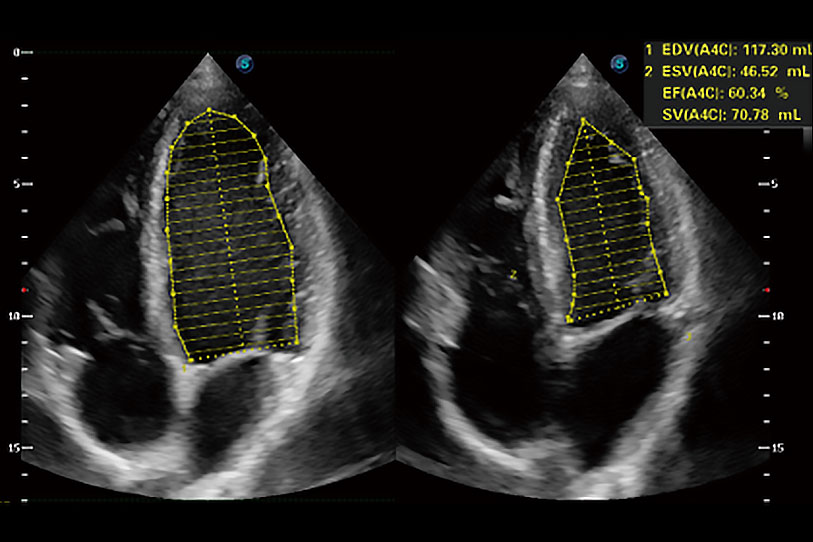

能夠基于左心室壁追蹤和辛普森法,自動(dòng)計(jì)算射血分?jǐn)?shù),支持多個(gè)可移動(dòng)點(diǎn)描跡,與手動(dòng)測(cè)量相比,極大節(jié)省了動(dòng)物醫(yī)生的時(shí)間和精力。

具備多種協(xié)議可選,同時(shí)支持17階段劃分法和專(zhuān)業(yè)的SE報(bào)告。